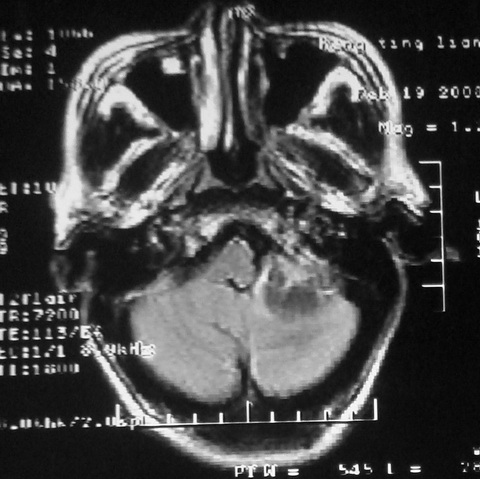

m,72,头疼,头晕两年,伴视力模糊三月,饮食呛咳两天。pe:颈部抵抗,左眼突出,左眼瞳孔约3mm,对光反射消失,双眼失明,伸舌困难,双肺呼吸音粗,心率110次/分,左上肢肌力i级,左下肢屈曲,肌张力高。现有08年2月19mri平扫及10年2月8日mri增强请会诊。ct病灶呈低密度伴散在点、片状等密度区,无明确钙化(无ct片资料可供上传)。[

脑外肿瘤,病灶呈匍匐蔓延,表皮样囊肿可能性大。

脑外肿瘤,病灶呈匍匐蔓延,表皮样囊肿可能性大。支持!